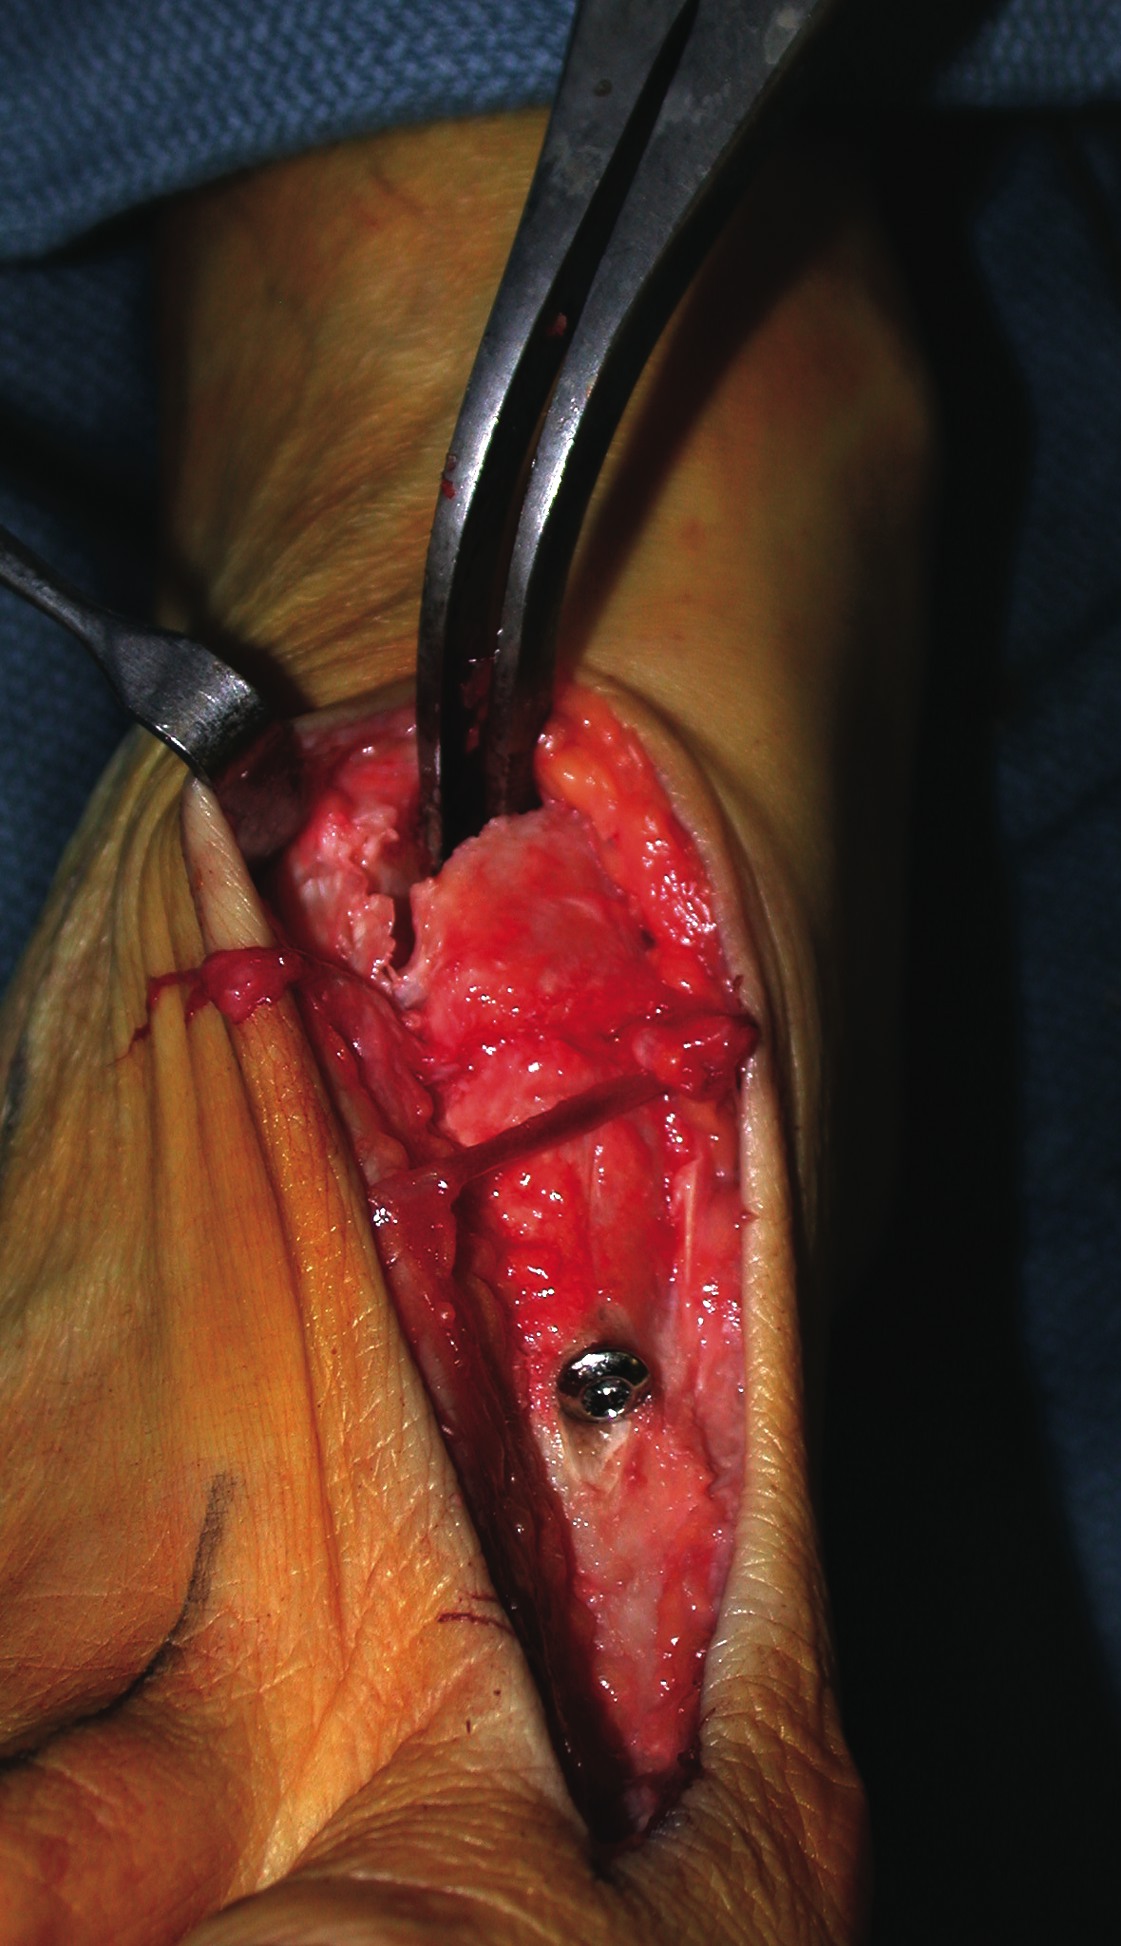

What You Should Know About The Intraoperative Hypermobility Test

Today, most surgeons perform a modified Lapidus procedure with an isolated first MCJ arthrodesis. One should accordingly perform an intraoperative evaluation after stabilizing the first MCJ and also assess the sagittal motion and transverse plane stability. While hypermobility is considered to predominately affect sagittal plane stability, some patients exhibit multiplanar instability. Splaying of the intermetatarsal angle indicates concomitant transverse plane instability and excessive sagittal plane motion indicates associated proximal hypermobility. The purpose of the intraoperative exam is to identify hypermobility in areas other than the first MCJ and to identify persistent transverse plane instability. One would perform the evaluation after correcting the intermetatarsal angle and fixating the first MCJ with screws. Evaluate overall sagittal excursion and metatarsal position in the method described above. One should compare the amount of motion to preoperative levels and correlate it with the clinical scenario. In some situations, additional joint fusions may be indicated. It should also be mentioned that overdissecting the lateral aspect of the medial cuneiform may temporarily destabilize the first intercuneiform joint and may be mistaken for persistent proximal hypermobility and/or transverse plane instability. Nonetheless, the sagittal plane motion should not increase after isolated fixation of the first MCJ. One must carefully assess persistent sagittal plane motion and correlate it with the clinical scenario. In some situations, additional joint fusions may be indicated. Clinicians can test transverse plane stability by placing an index finger between the metatarsal heads in the first interspace after performing the first MCJ fusion. The metatarsal heads should be situated close together.14 If the metatarsals splay open, then proximal transverse plane instability exists. Of course, the intermetatarsal angle must be reduced for this test to be valid. Excessive persistent transverse plane instability is less forgiving since additional fusions are often necessary to prevent the intermetatarsal angle from splaying. This is especially important when treating hallux valgus because the bunion will likely return and the patient may consider it a failed surgery. McInnes and Bouche attributed intercuneiform diastasis to one case (of 32 feet) of recurrent metatarsus primus adductus after an isolated first MCJ fusion, which the patient rated as “ineffective.”14